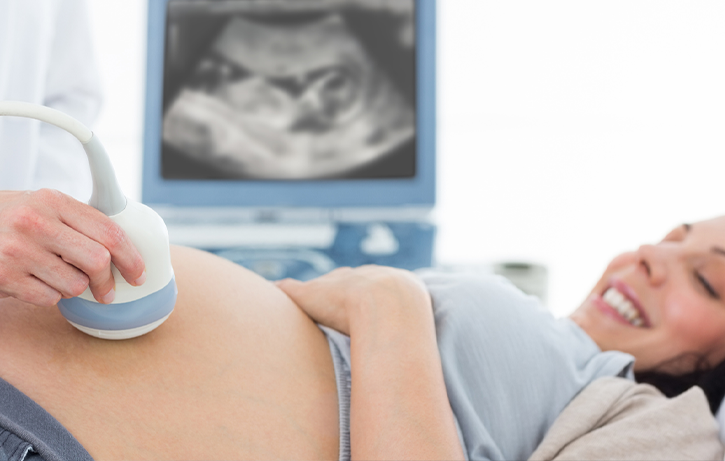

Women's Imaging

Our Commitment to You… Providing Individualized, Innovative and Nurturing Healthcare for WomenWomen's Imaging

Our Commitment to You…..

Providing Individualized, Innovative and Nurturing Healthcare for Women

To keep this commitment, our Radiologists, Technologists, and Medical Assistants are closely involved in the diagnostic exam of each patient. By taking a special interest in each and every patient, we can help ensure quality care.